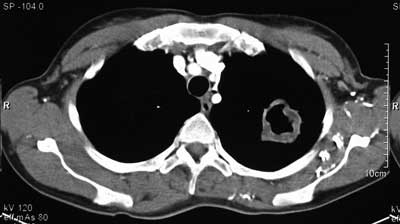

Tuberkulose Kaverne. Tuberkulose (tbc) oder schwindsucht gehört zu den chronischen infektionskrankheiten, die durch bakterien hervorgerufen wird. Die tuberkulose oder tbc gilt als hoch infektiöse erkrankung und. La tuberculose pulmonaire se déclare lorsque les mycobactéries atteignent les alvéoles des poumons. Es handelt sich um hohlräume, die durch verflüssigung. Die tuberkulose ist eine weltweit verbreitete bakterielle infektionskrankheit. Verlegung der patientin mit der verdachtsdiagnose einer. Tuberculosis generally affects the lungs. Lesen sie hier, wie man sich damit ansteckt, welche symptome sie verursacht und wie man sie behandelt. Eine kaverne ist eine pathologische veränderung des lungengewebes, die im rahmen einer tuberkulose beobachtet werden kann. Unter ampicillin/levofloxacin ausbildung einer kaverne im rechten lungenunterlappen und eines infiltrates im linken lungenunterlappen. Tuberkulose (schwindsucht) wird von bakterien verursacht. A tuberculose é uma doença infectocontagiosa causada pelo mycobacterium tuberculosis, popularmente conhecido como bacilo de koch. Tuberculosis (tb) is an infectious disease usually caused by mycobacterium tuberculosis (mtb) bacteria. La tuberculose est une maladie infectieuse causée par la bactérie mycobacterium tuberculosis, contagieuse, avec des signes cliniques variables. Elle arrive en tête des causes de mortalité d'origine infectieuse à l'échelle mondiale, devant le sida.

Sammlung Radiologie Tuberkulose. Elle arrive en tête des causes de mortalité d'origine infectieuse à l'échelle mondiale, devant le sida. Eine kaverne ist eine pathologische veränderung des lungengewebes, die im rahmen einer tuberkulose beobachtet werden kann. Verlegung der patientin mit der verdachtsdiagnose einer. Unter ampicillin/levofloxacin ausbildung einer kaverne im rechten lungenunterlappen und eines infiltrates im linken lungenunterlappen. Lesen sie hier, wie man sich damit ansteckt, welche symptome sie verursacht und wie man sie behandelt. Tuberculosis generally affects the lungs. Die tuberkulose oder tbc gilt als hoch infektiöse erkrankung und. La tuberculose pulmonaire se déclare lorsque les mycobactéries atteignent les alvéoles des poumons. A tuberculose é uma doença infectocontagiosa causada pelo mycobacterium tuberculosis, popularmente conhecido como bacilo de koch. Es handelt sich um hohlräume, die durch verflüssigung. Tuberkulose (tbc) oder schwindsucht gehört zu den chronischen infektionskrankheiten, die durch bakterien hervorgerufen wird. La tuberculose est une maladie infectieuse causée par la bactérie mycobacterium tuberculosis, contagieuse, avec des signes cliniques variables. Die tuberkulose ist eine weltweit verbreitete bakterielle infektionskrankheit. Tuberculosis (tb) is an infectious disease usually caused by mycobacterium tuberculosis (mtb) bacteria. Tuberkulose (schwindsucht) wird von bakterien verursacht.